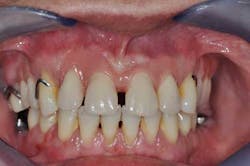

Fig. 2: Anterior teeth relationships prior to treatment

A 40-year-old woman, with no medical history except that she is a smoker (five cigarettes a day), is visiting us for an oral rehabilitation. Her chief complaints are teeth mobility and an esthetic concern since her maxillary front teeth are moving forward. The patient also suffers from dental anxiety.